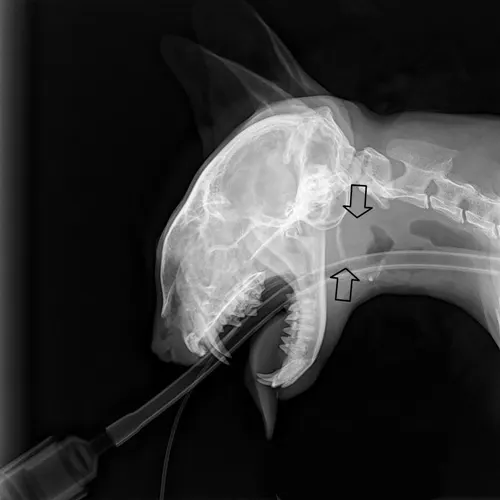

Chest radiography can rule out lower respiratory and metastatic disease (if malignancy is suspected). Skull radiographs —including open-mouth, lateral, lateral oblique (left and right), and ventrodorsal views—are also obtained (Figures 2 and 3). False-negative results are common with bulla radiographs. Computer tomography (CT) is sensitive for the detection of middle ear involvement.

FIGURE 3 The very large soft tissue density (arrows) in the pharyngeal region of this lateral skull radiograph represents a large inflammatory polyp.